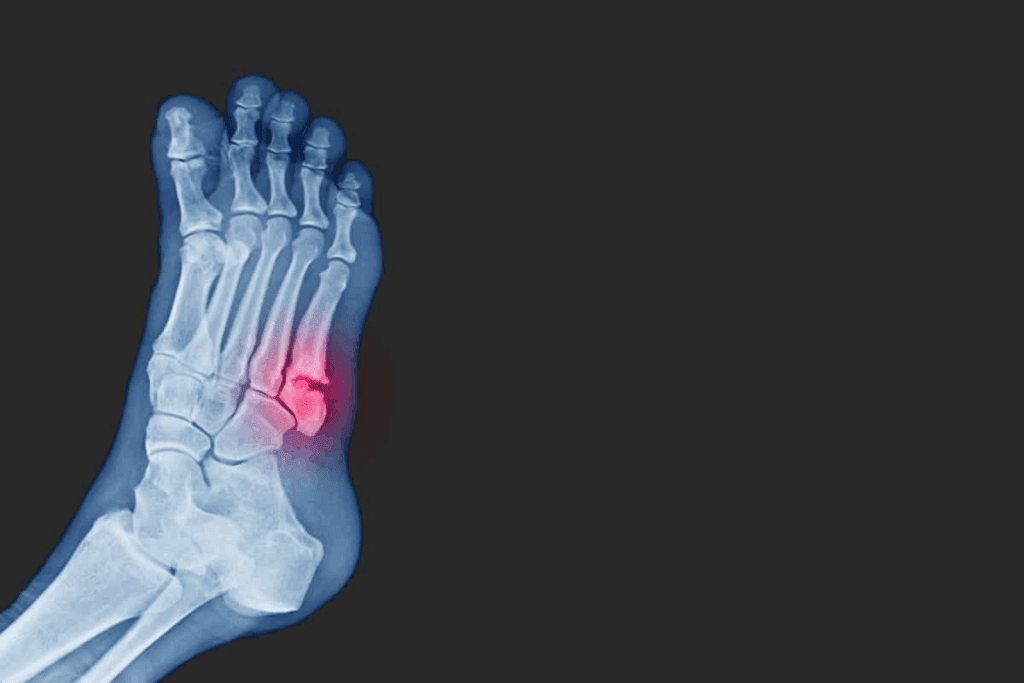

Identifying Fracture Problems in Different Body Parts

It’s key to know the unique issues with fractures in different body parts for the right treatment. Fractures can happen anywhere in the body. Their problems change a lot based on where and how bad the injury is.

Lower Extremity Fracture Complications

Fractures in the legs, ankles, and feet have their own challenges. Complications can include:

- Difficulty bearing weight on the affected limb

- Increased risk of deep vein thrombosis (DVT)

- Chronic pain or instability in the ankle or knee

Lower extremity fractures are serious because these limbs bear our weight. Issues like osteomyelitis, an infection of the bone, can be very dangerous if not treated quickly.